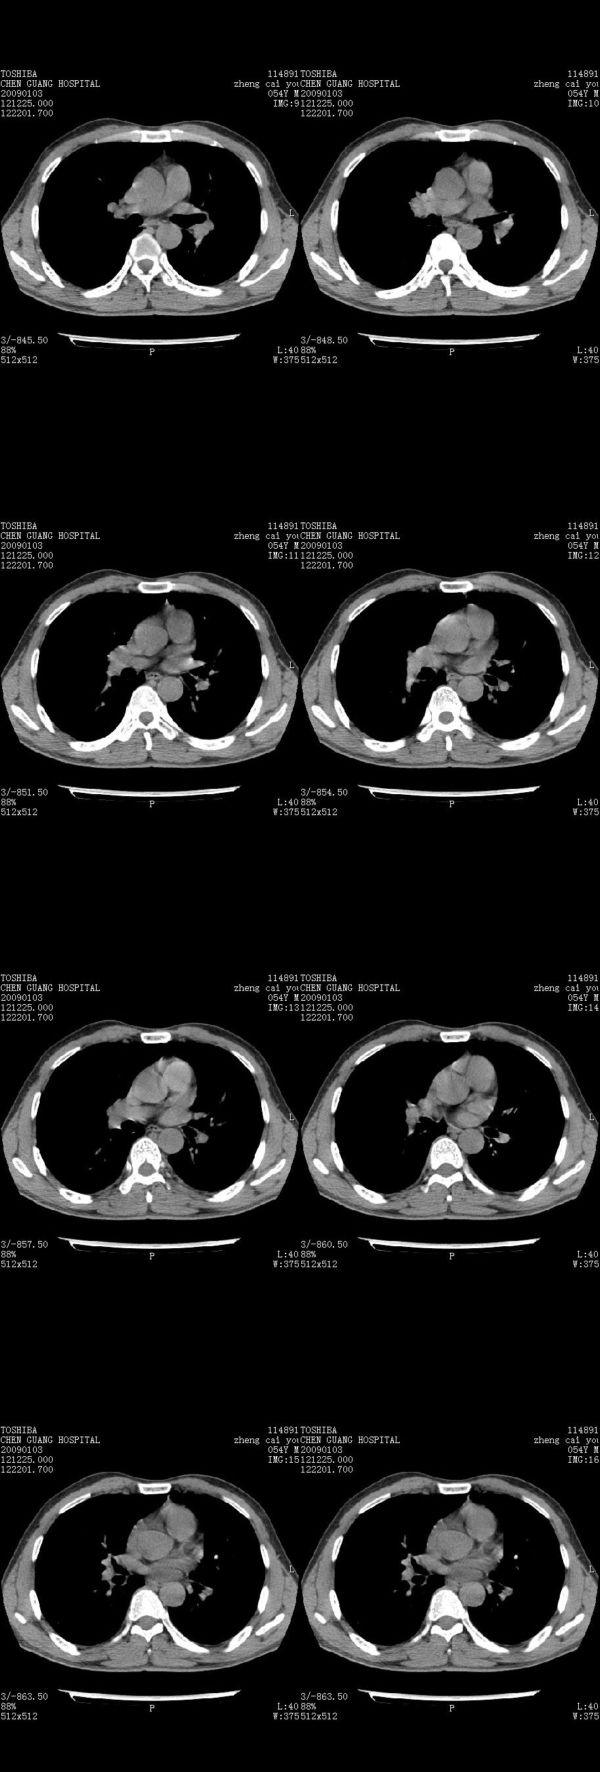

男,54岁,右侧胸部疼痛,平时吸烟,有抽烟后咳嗽咯痰史。昨天没把xiphoid软件吃懂,所以没把纵隔窗图像处理出来!请各位老师帮忙看一下右肺门有没有问题?谢谢!!!!!!!!!!

我同学讲红线部分强化不好,感觉不是很舒服,这是什么道理?

我同学讲红线部分强化不好,感觉不是很舒服,应该 是软组织间隙,不是一个孤立的病灶。

气管前腔静脉后似见增大淋巴结影,肺门区未见明显肿块影。肺窗示右肺中叶外侧段透亮度增高,可过一段时间再查一下对比一下,毕竟是自己的至亲,又有条件,辐射就顾不得了。

也觉得还好吧,只是右下肺动脉显粗了点,纵膈有钙化淋巴结,再有肺窗就更好了

各位老师:奇静脉增宽,肺上未见明显实变,这还需注意观察些什么?????

右侧肺门影增大,不除外增大淋巴结可能